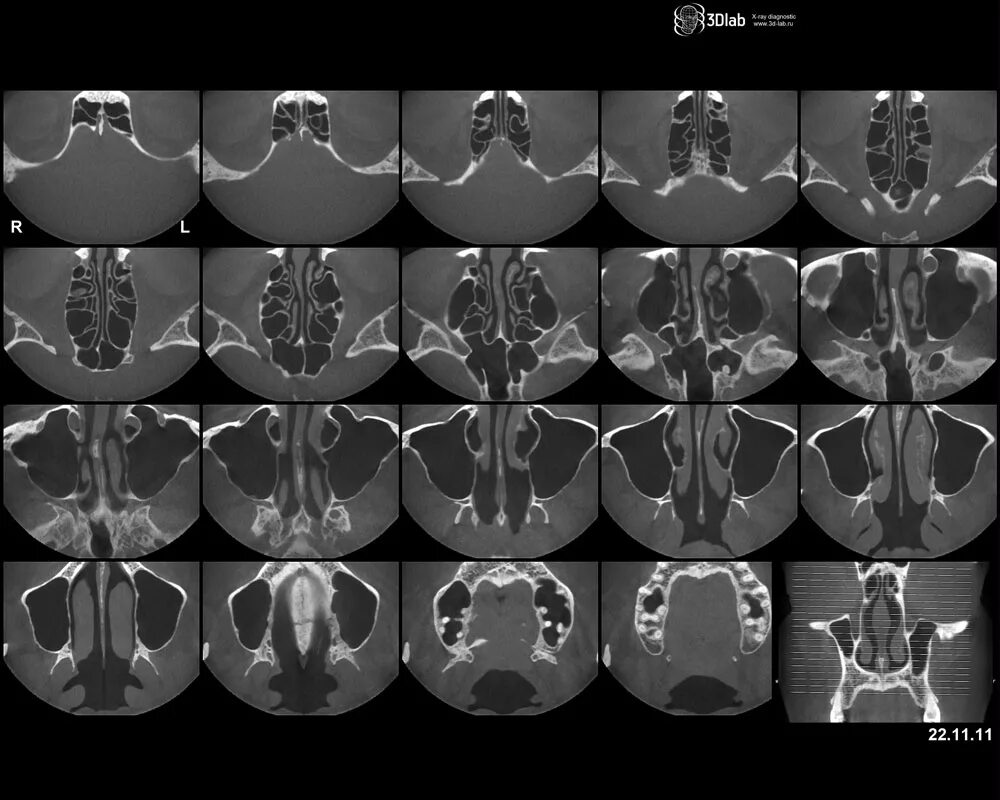

Кт онп что это